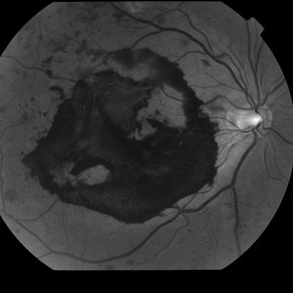

Proliferative Diabetic Retinopathy with Subhyaloid hemorrhage

Oct 18 2012 by Suber S. Huang, MD, MBA, FASRS

43 year old diabetic man with proliferative diabetic retinopahty, subhyaloid hemorrhage, ischemia, neovascuarization.

Photographer: Stacie Hrvatin

Condition/keywords: ischemia, retinal neovascularization, subhyaloid hemorrhage